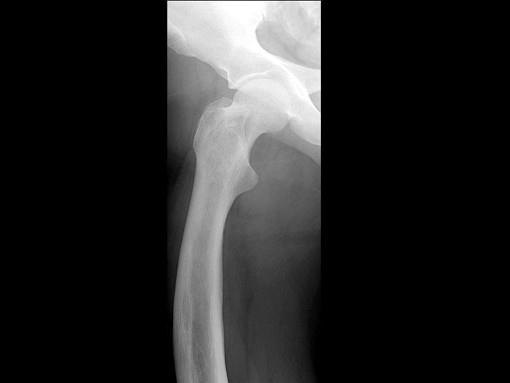

问题 男,67岁,右侧股骨痛,结合图像,最可能的诊断是?(?)

选项 A.骨纤维结构不良 B.维生素D缺乏病 C.成骨不全 D.软骨发育不全 E.畸形性骨炎

答案 E